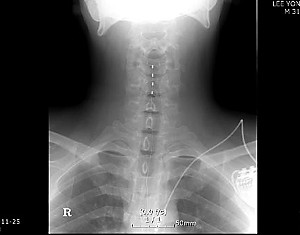

‘CRPS(Complex regional pain syndrome)’는 팔, 다리 등에 입은 신체의 어느 한 부분에 극심한 통증이 지속적으로 나타나는 질환이다. 통증이 언제 올지도 모른다. 왔다하면 ‘불에 타는 듯한’ ‘송곳으로 찌르거나 긁어내리는 듯한’ 엄청난 아픔을 느낀다. 삶의 매일 매일, 매순간이 ‘공포’다. 치료도 쉽지 않아 이런 상태로 수년 혹은 평생을 살아야 하기도 한다. 산업재해를 인정받는 것도 힘겹다. 장애등급 신청은 받아들여지지 않는다. 전문가에 따르면 치료 중 스스로 목숨을 끊는 사례가 나오기도 한다. CRPS 환자들 만나 그들의 눈물과 한숨을 들어봤다.

현재 김씨는 손가락에서 시작된 통증이 어깨까지 퍼져 왼쪽 손과 팔을 사용하지 못하는 상태다. CRPS는 이처럼 ‘2차 증상’을 부르기도 한다. CRPS 환자들에게 흔히 동반되는 골다공증을 피하고자 열심히 받았던 재활도 중단했다. 과거 왼손잡이였던 김씨가 실생활에서 느낄 불편함은 짐작하기 어려울 정도다.